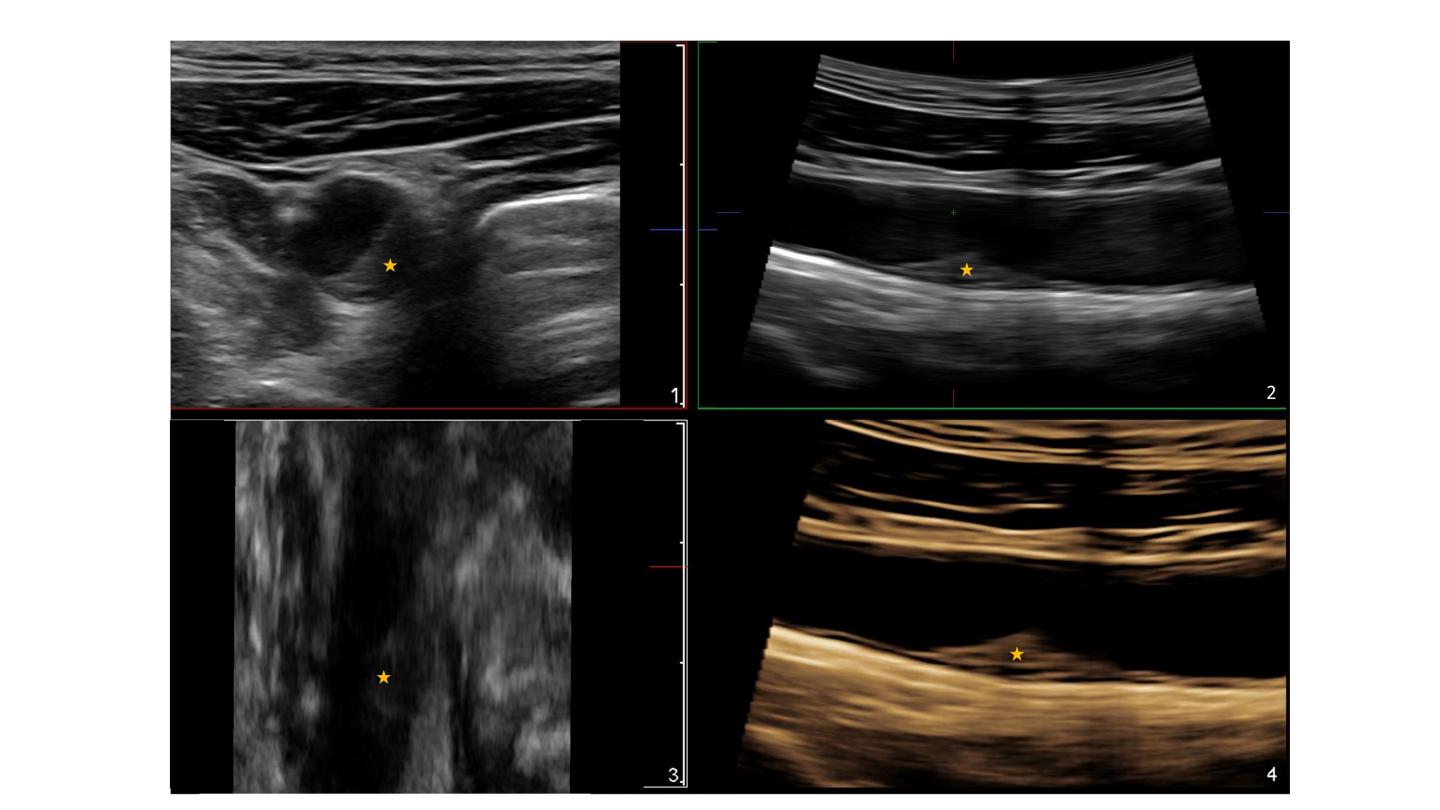

image: Asterisks indicate the presence of an atherosclerotic plaque in the common carotid artery detected by 3D ultrasound. The plaque does not cause significant obstruction of the artery (

The simpler imaging techniques like 2D and 3D ultrasound are accessible and do not involve exposure to radiation. With these techniques, explains CNIC Clinical Research Director Dr Borja Ibañez, "we can detect and quantify the burden and volume of atherosclerotic disease and precisely monitor its progression, thus identifying individuals who stand to benefit from earlier and more intensive prevention."

The JACC article presents a 3-year follow-up study of the PESA cohort that makes the first direct comparison between these two imaging-based risk markers: coronary calcium by CT and atherosclerosis burden in the carotid and femoral arteries by 2D and 3D ultrasound. "The results show that ultrasound of the peripheral arteries is a more efficient method for detecting atherosclerosis progression than the study of coronary calcium by CT," said lead author Dr Beatriz López-Melgar.